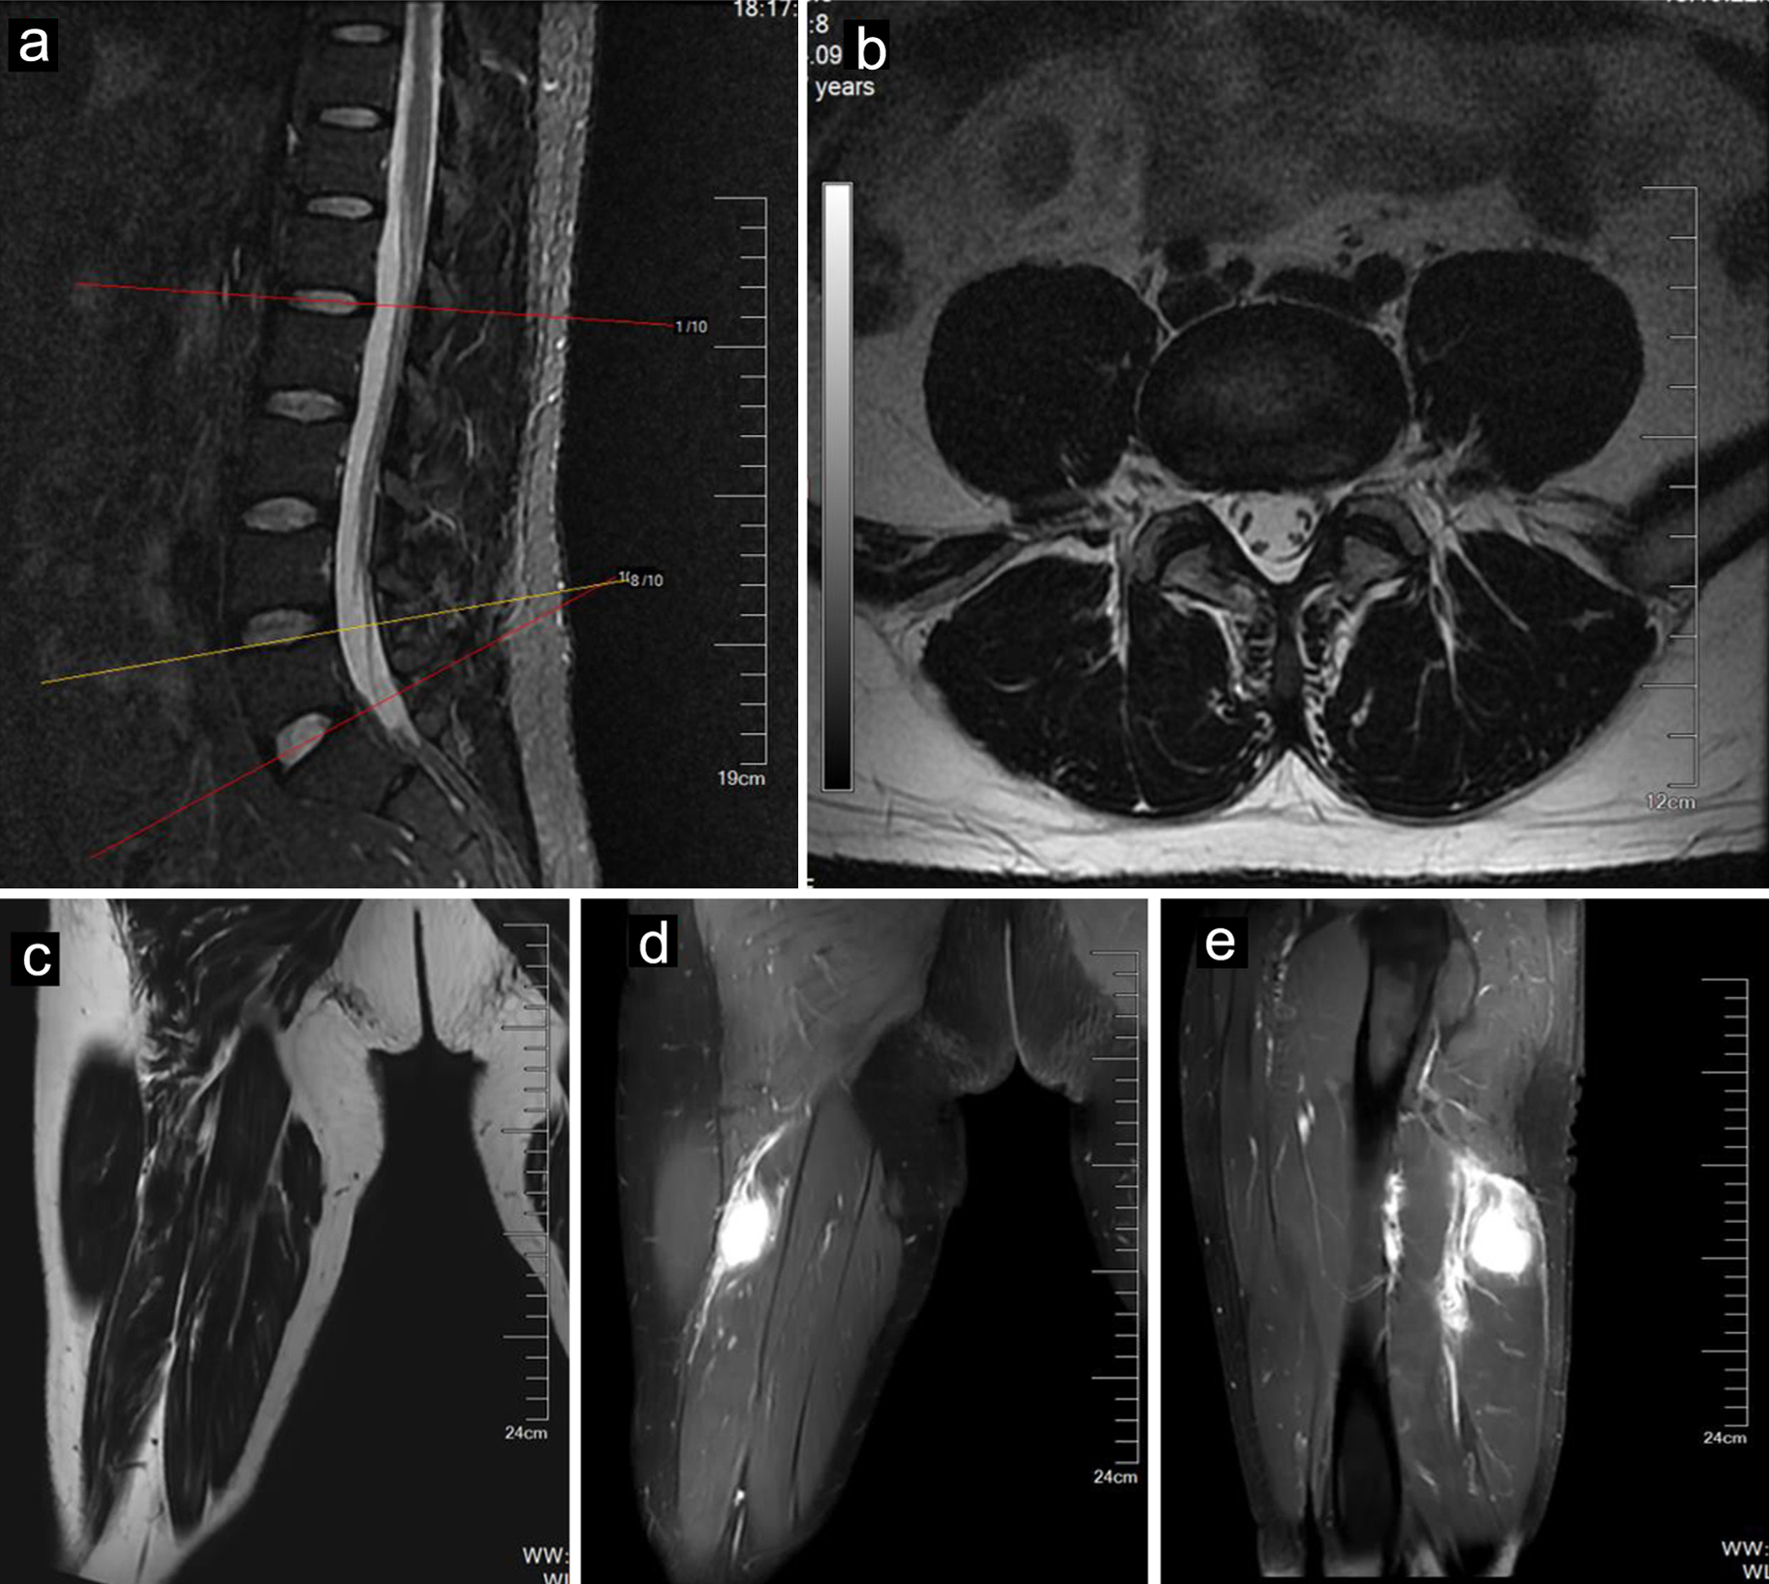

A 40-year-old man whose job was a bus driver was referred to our clinic for orthopedic evaluation. He complained of low back pain with the pain radiating to his right leg. His symptoms worsened during the past 2 months. He was diagnosed with LDH at another hospital. Many conservative treatments, including physical therapy and a root block at the outlet of the piriformis, were used, but these treatments were ineffective, and the patient’s symptoms continued to progress. On neurologic examination, his right big toe dorsiflexion weakness (motor power: grade 4) and sensory impairment were noted in the L5 dermatome, whose symptoms mimicked LDH. His Lasegue sign in the right leg was positive, but bilateral Babinski sign was negative. His laboratory studies on admission were unremarkable. Magnetic resonance imaging (MRI) revealed a mildly herniated lumbar disc at L4-L5 without significant compression of the nerve roots of L5 or deformation of the spinal cord (Fig. 1a, b). Until now, we found that the diagnosis of LDH could not completely explain his progressive symptoms.

![]() Click for large image | Figure 1. MR images of a 40-year-old male with IMT. Sagittal (a) and axial (b) MR images of the lumbar spine showing a mildly herniated disc at the L4-L5 level. The tumor (arrows) showed mild hyperintensity on T1-weighted imaging (c) and hyperintensity on fat-suppressed T2-weighted imaging (d). The tumor (arrows) showed enhancement after contrast agent injection (e). IMT: inflammatory myofibroblastic tumor; MR: magnetic resonance. |

Therefore, his symptoms prompted us to conduct supplementary physical exams, which revealed a positive Tinel’s sign in the posterior right thigh. We thus conducted further evaluations, such as computed tomography (CT) and MRI of the right thigh, which revealed a mass along the right sciatic nerve (Fig. 1c, d). Finally, surgery was arranged for the patient to remove the mass. During surgery, the mass was found to originate from the sciatic nerve (Fig. 2a). A section of the mass was sent for pathology (Fig. 2b), and the tumor was negative for smooth muscle actin (SMA), S-100 and CD34 (Fig. 2d-f). The mass was histologically confirmed to be an IMT, which is rarely present in the peripheral nerves.